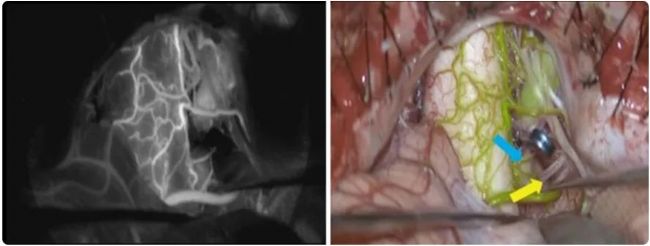

雖然可以通過常規的術中吲哚菁綠視頻血管造影識別腦干、神經和血管,但無法看到穿支血流(圖 2,左)。GLOW800 AR 應用程序提供了增強的信息,幫助正確評估通往腦干的穿支血流,并且在保持對腦干、神經和血管的直接視線的同時可以完成夾閉(圖 2,右)。

圖 2:部分血栓形成的大型椎動脈動脈瘤。左:通過黑白 ICG 成像評估近端椎動脈夾閉。右:通過實時 ICG 評估近端椎動脈夾閉。